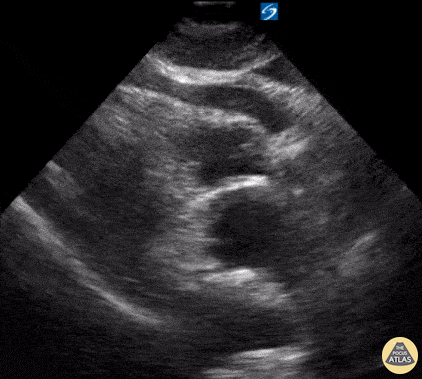

Pericardial Disease - Cardiac Tamponade secondary to Type A Aortic Dissection

A 72-year-old male presented with syncope and was found to be hypotensive. POCUS revealed a large, circumferential pericardial effusion with tamponade physiology. Additional workup including chest CT revealed POCUS findings to be the consequence of a Type A aortic dissection (with blood extending back into the pericardial sac). Dr. John Cook, @J_County Dr. Tim Scheel, @tscheelEMUS